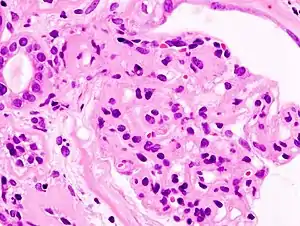

| Microscopic image of diabetic glomerulosclerosis, the main cause of nephrotic syndrome in adults. | |

Secondary causes of nephrotic syndrome have the same histologic patterns as the primary causes, though they may exhibit some differences suggesting a secondary cause, such as inclusion bodies.[24] They are usually described by the underlying cause, such as:

- Diabetic nephropathy: is a complication that occurs in some diabetics. Excess blood sugar accumulates in the kidney causing them to become inflamed and unable to carry out their normal function. This leads to the leakage of proteins into the urine.